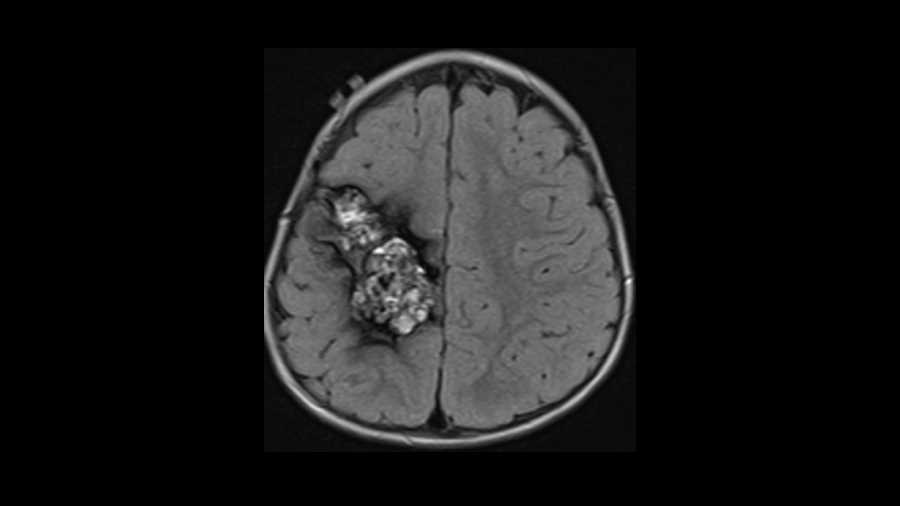

Angiomyolipoma (AML)

This young adult presented with fever and night sweats. On imaging we see mild symmetric enlargement of the cervical lymph nodes and diffuse enlargement of the lymphoid tissue comprising Waldeyer s ring which is composed of the nasopharyngeal adenoids, palatine tonsils, lingual tonsils. This patient had an abnormal peripheral blood smear and bone marrow biopsy with a diagnosis of acute myelocytic leukemia. Lymph nodes in leukemia have similar characteristics to lymphoma. They can be large, are usually non-necrotic, and relatively symmetric indicating a systemic process. Differential considerations for the enlargement of Waldeyer s ring include reactive tonsillar lymphoid hyperplasia as in HIV, squamous cell carcinoma, or extra-nodal non-Hodgkins lymphoma of Waldeyer s lymphatic ring which is the most common site.